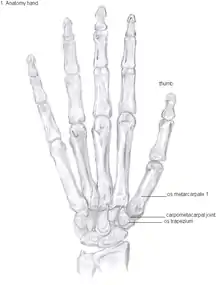

Anatomy

The TMC joint is a synovial joint between the trapezium bone of the wrist and the metacarpal bone at the base of the thumb. This joint is a so-called saddle joint (articulatio sellaris), unlike the CMC joints of the other four fingers which are ellipsoid joints.[17] This means that the surfaces of the TMC joint are both concave and convex.

This shape provides the TMC joint a wide range of motion. Movements include:[18]

The TMC joint is stabilized by 16 ligaments.[19] Of these ligaments, the deep anterior oblique ligament, also known as the palmar beak ligament, is considered to be the most important stabilizing ligament.[20]